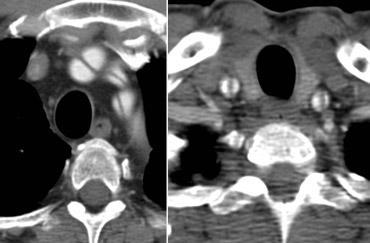

Bóc tách Type B. Mũi tên xanh lá chỉ điểm vào. Lòng giả được chỉ bởi các mũi tên vàng và thấy xoắn quanh lòng thật.

Khi có 2 lòng mạch, chúng sẽ xoắn quanh nhau (hình minh họa).

Bên trái là các hình ảnh liên tiếp của một bóc tách Type B.

Lòng thật được bao quanh bởi các vôi hóa.

Lòng thật nhỏ hơn vì lòng giả chèn ép quanh lòng thật do áp lực tâm thu liên tục (gọi là dấu hiệu Mỏ chim – Beak-sign).